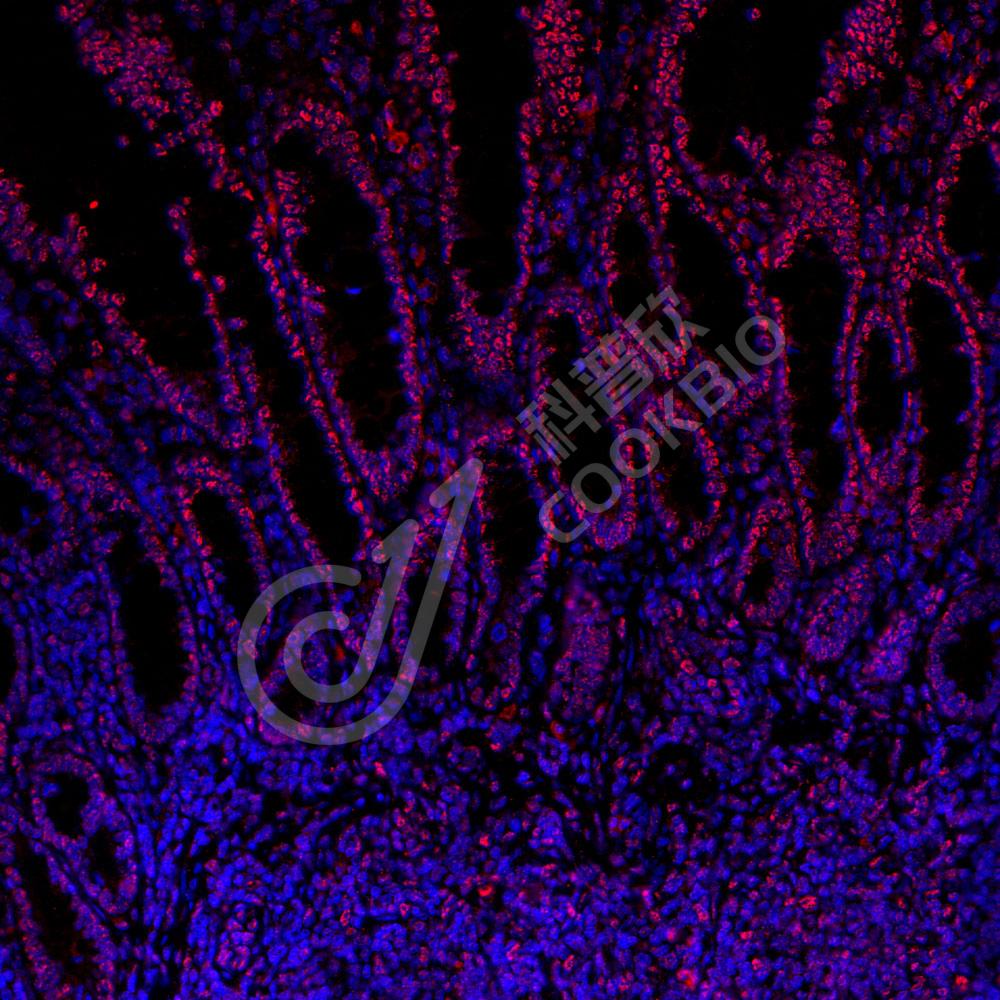

IF检测PMS2蛋白(货号 K2360003)(红色).

样品: 人结肠, 4%多聚甲醛 (货号KSG1101) 固定12-24小时.

抗原修复: 柠檬酸抗原修复液(干粉, pH 6.0) (KSG1201), 高压锅均匀喷气计时2分钟.

封闭: 3% BSA(货号KSGC305010)的PBS溶液, 室温孵育30分钟.

—抗: 1: 800稀释, 4℃ 孵育过夜.

二抗: Cy3标记山羊抗小鼠IgG (H+L) (货号KB63903), 1: 300稀释, 室温孵育1小时.